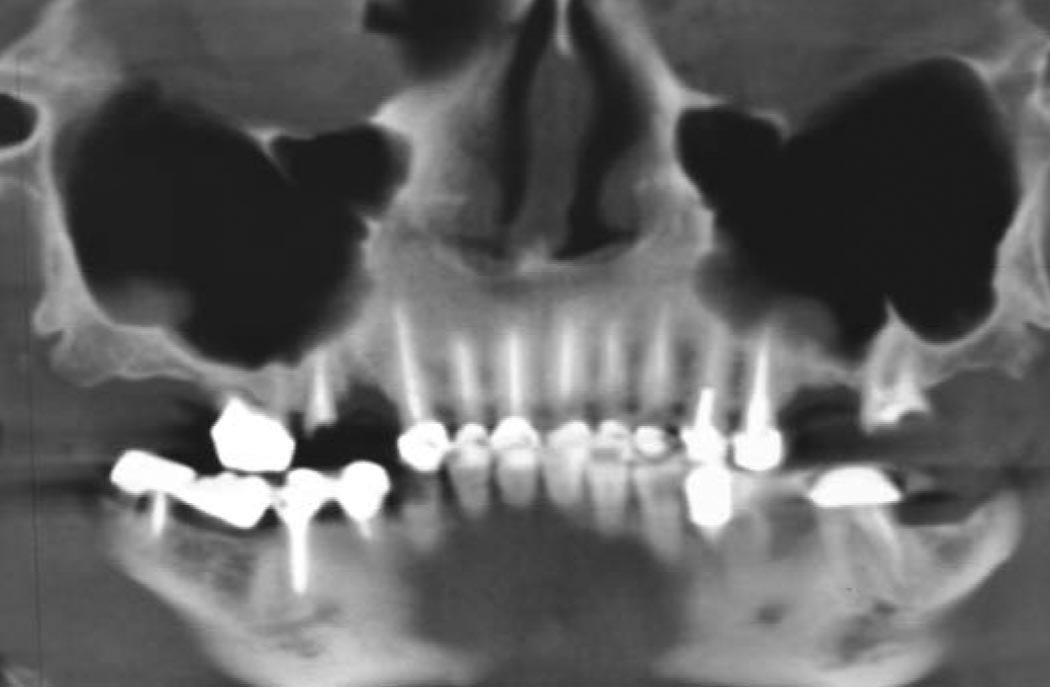

C'est pourquoi, le dentiste à Cannes adapte la longueur, le diamètre et la forme de l'implant au cas clinique grâce à un examen radiologique performant: 3D ou scanner.

L'implantologiste va, à l 'aide de forets de diamètre adapté, préparer la place dans l'os. L'implant réalisé au sein de notre cabinet dentaire à Cannes pénètre dans l'os en forçant légèrement. L'implant cannes est ainsi stabilisé. Après la pose de l'implant cannes va avoir lieu la phase d'ostéo-intégration. En effet l'implant, contrairement à la dent, est totalement fixe, c'est-à-dire ankylosé dans l'os. La mise en charge de l'implant est généralement différée pour permettre la phase d'ostéo-intégration (de plusieurs semaines à plusieurs mois). Par la suite, une couronne sera mise sur cet implant qui se comportera comme une racine artificielle.